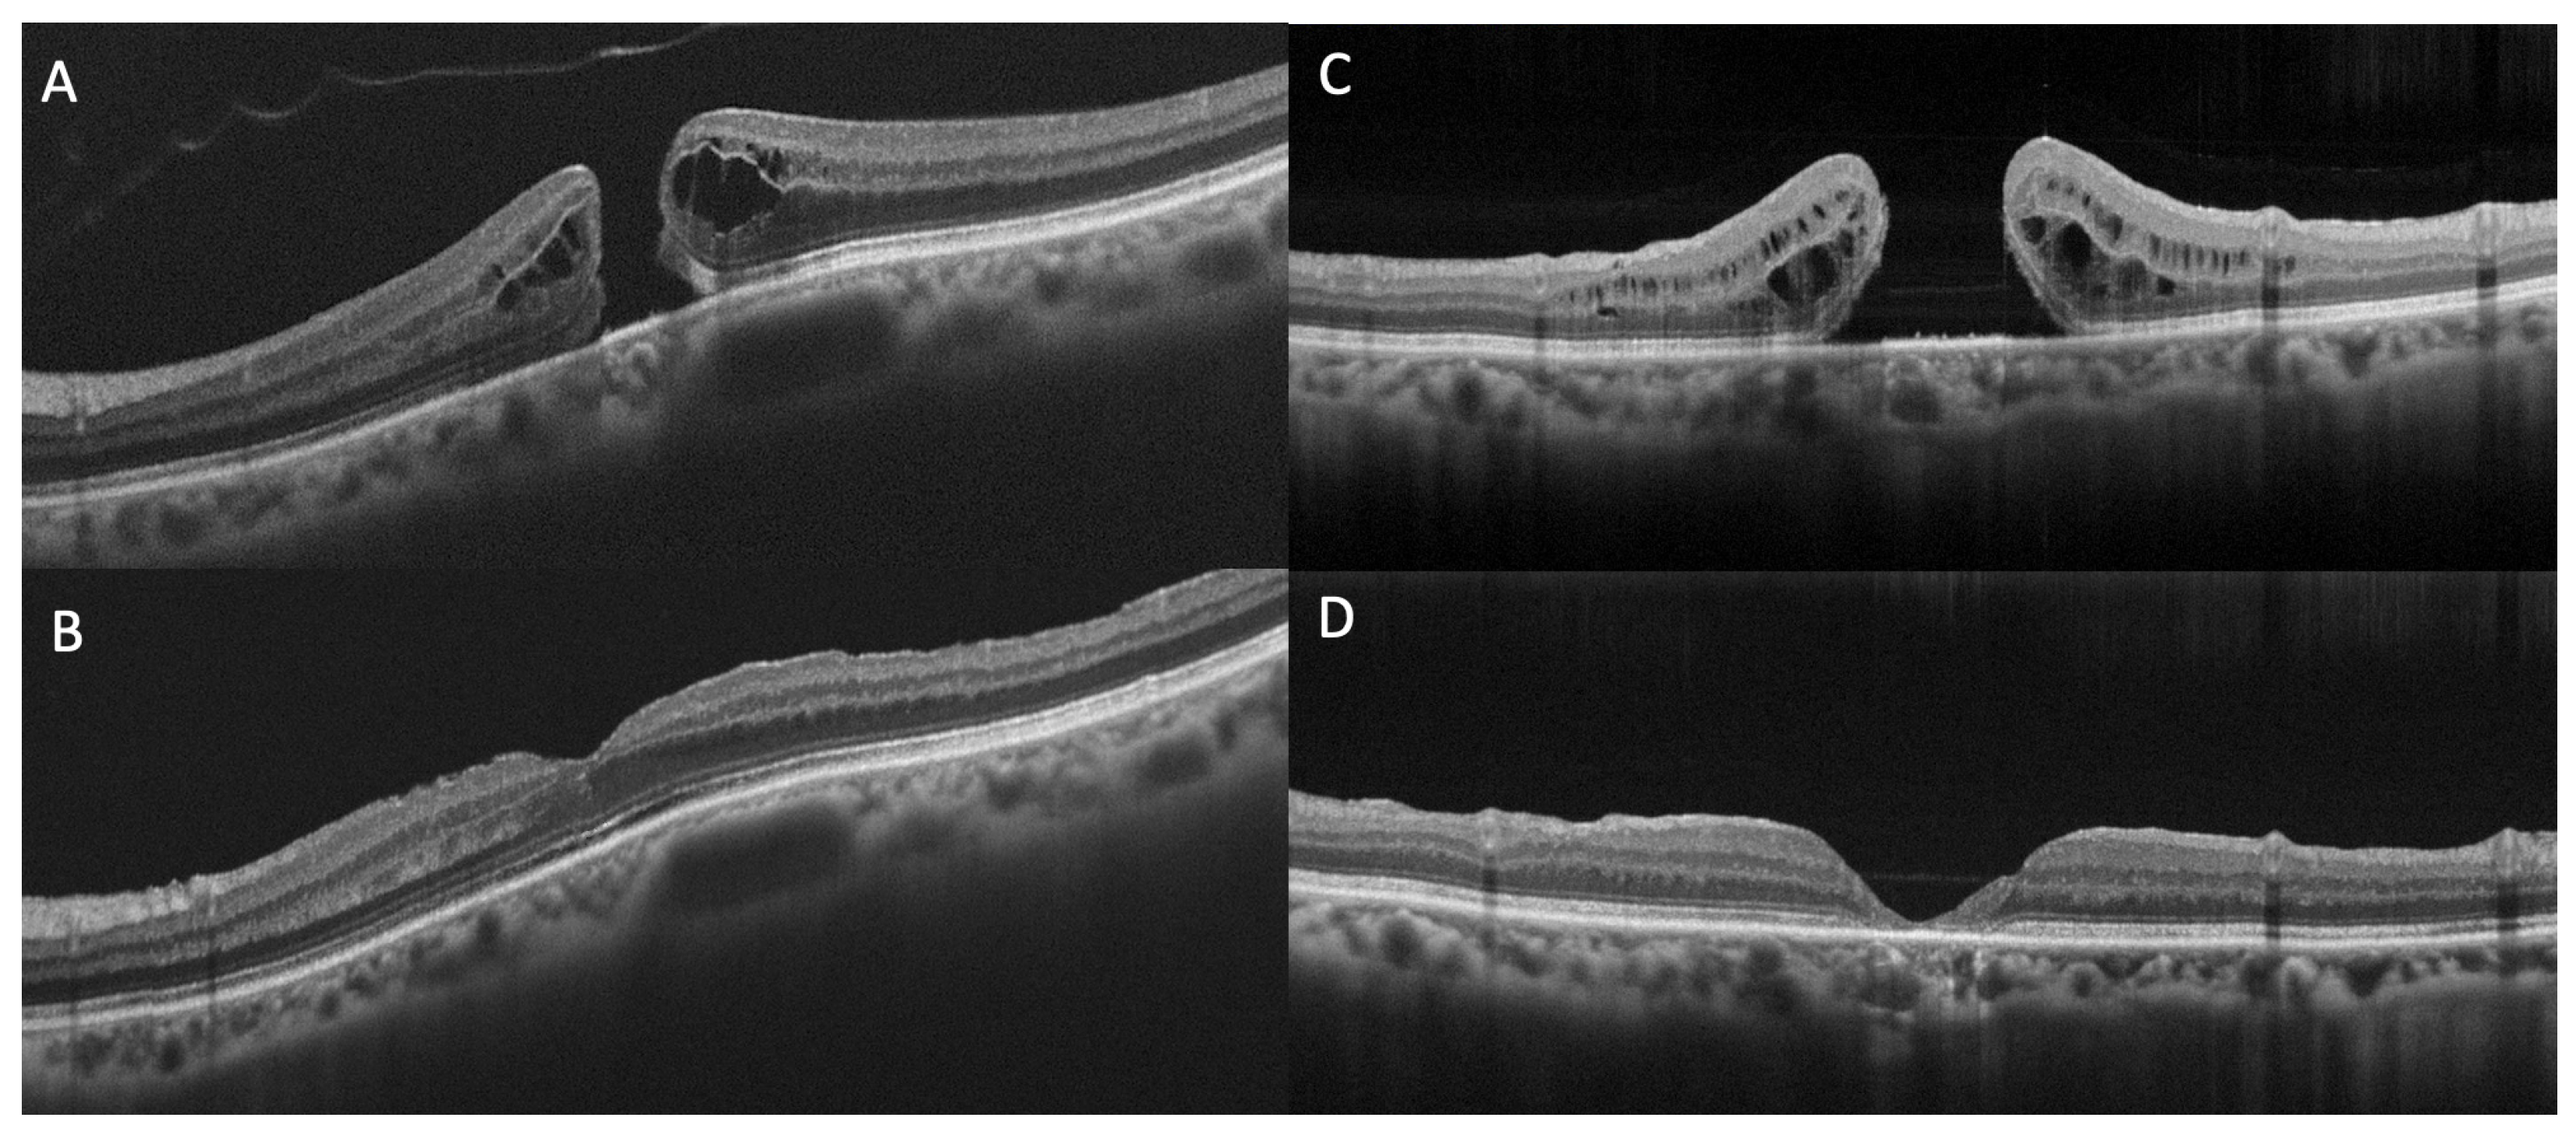

Concerning the external retinal layers, structural OCT allows the delineation of three hyperreflective bands: the external limiting membrane (ELM), the ellipsoid zone (EZ), and the interdigitation zone (IZ) [20]. The EZ and IZ were previously known as the junction of the inner and outer photoreceptor segments (inner segment (IS)/ outer segment (OS) junction) and the cone outer segment tips line, respectively [21]. Numerous works have investigated the correlation between preoperative defects and/or postoperative remodeling of the ELM, EZ, and IZ and VA in patients with FTMHs (Figure 2) [22,23,24,25]. There is a consensus in the literature that the restoration of these three bands is correlated with VA [26,27]. Houly et al. quantitatively evaluated the correlation between the length of preoperative defects of the three bands and VA at 3 and 6 months after surgery, finding a significant association [28]. In particular, the preoperative length of the ELM defect was found as the strongest predictor of VA after FTMH surgery.

Figure 2.

Optical Coherence Tomography (OCT) scans of full-thickness macular holes and defects in external limiting membrane (ELM), ellipsoid zone (EZ), and interdigitation zone (IZ) at baseline (A,C) and at six months follow-up (B,D). (A) Preoperative ELM, EZ and IZ are almost preserved and at postoperative follow-up (B) a quite full subfoveal restoration of the three bands can be appreciated. (C) Preoperative ELM, EZ and IZ defects are extensive and at postoperative follow-up (D) subfoveal atrophy development can be observed.